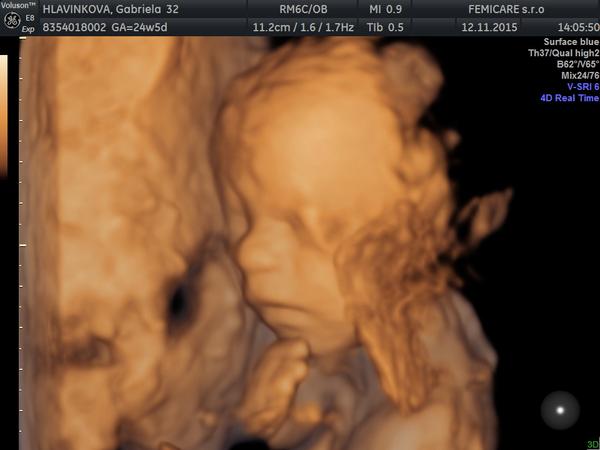

Súhlasím.. Naj doktor asi 🙂 milý, všetko povie s úsmevom, naša malá vtedy vraj nemala náladu sa fotiť a aj tak... Podarilo sa mu 🙂 pridávam zopár foto, 25 týždeň to bol

@gabuchah ňuňuška krásna malinká 🙂 pridávam aj našú foto z 20. tt